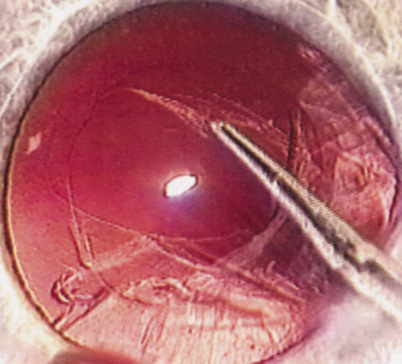

Hydrodissection can be performed after the surgeon has successfully completed capsulorrhexis.97 If the capsulorrhexis is not intact, fluid forced around the interior of the capsule may cause the bag to splay open. With capsulorrhexis, hydrodissection is a safe and extremely useful maneuver. Hydrodissection can be thought of as two maneuvers: hydrodelineation and cortical cleaving hydrodissection. By placing a 27-gauge cannula on a syringe filled with balanced saline solution (BSS), the surgeon can direct fluid beneath the residual anterior capsular rim to create a cleavage plane. Depending on the direction the fluid wave takes, different lamellae of the cataract will be separated. Hydrodelineation is the term used when the cleavage plane separates the adult nucleus from the fetal nucleus or the adult nucleus from the more peripheral epinucleus. Hydrodelineation often results in the characteristic golden ring sign (Fig. 11). Cortical cleavage occurs when the cortex is separated from the capsular bag (Fig. 12). Finding the cortical cleavage plane may be facilitated by gently lifting the capsular margin away from the cortex with the BSS cannula before injecting. Several small bursts of fluid allow the surgeon to monitor progress of the fluid wave. When dealing with a soft nucleus, the authors strive to perform true cortical cleaving hydrodissection. For a hard nucleus, hydrodelineation allows manipulation of less of the nuclear bulk, although the remaining epinuclear shell must be addressed in an additional step. Hydrodelineation is particularly useful if the nucleus is not freely mobile after cortical cleaving hydrodissection.

Fig. 11. A crisp “golden ring” is seen from the fluid cleft between the epinucleus and nucleus with hydrodelineation.